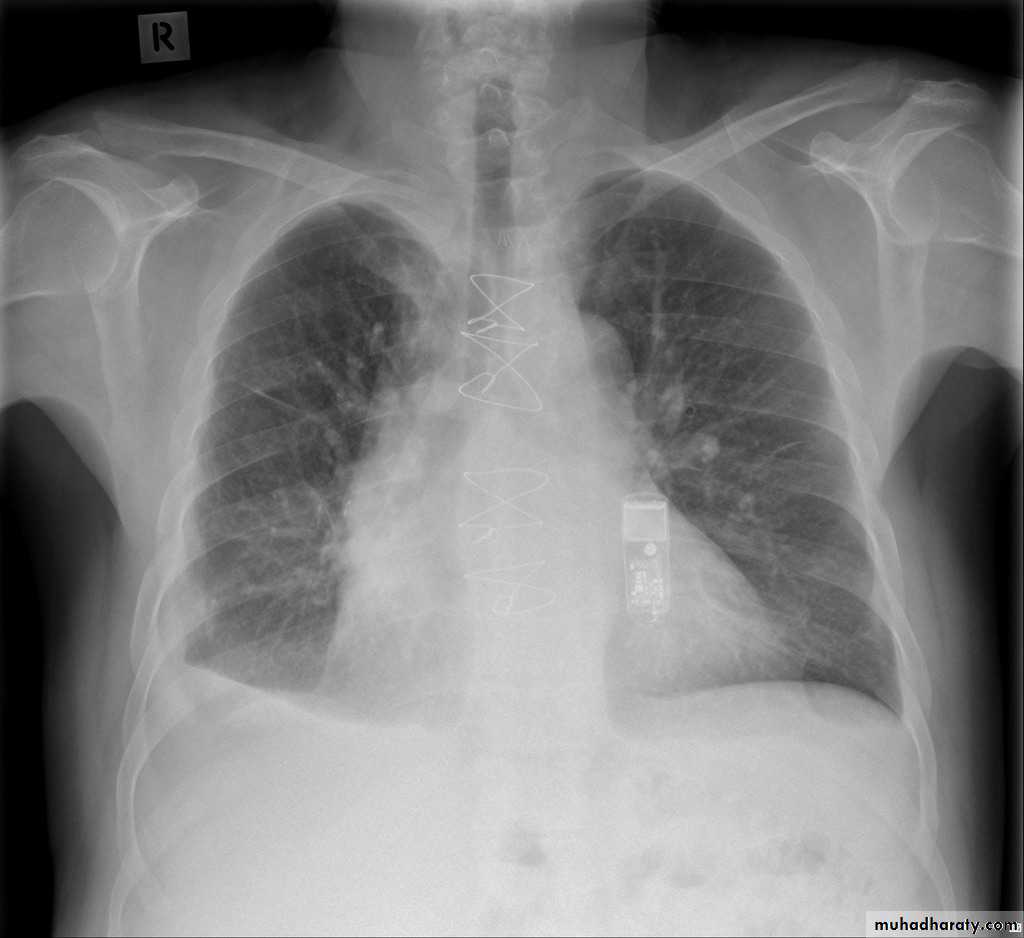

Pulmonary emphysema is defined as the "abnormal permanent enlargement of the airspaces distal to the terminal bronchioles accompanied by destruction of the alveolar wall and without obvious fibrosis". Emphysema is one of the entities grouped together as chronic obstructive pulmonary diseaseRadiographic features

Plain film

Except in the case of very advanced disease with bulla formation, chest radiography does not image emphysema directly, but rather infers the diagnosis due to associated features :

hyperinflation:

1.flattened hemidiaphragm(s): most reliable sign

2.ncreased and usually irregular radiolucency of the lungs

3.increased retrosternal airspace

4.increased antero-posterior diameter of chest

5.widely spaced ribs

6.sternal bowing

7.tenting of the diaphragm

8.saber-sheath trachea

9.vascular changes paucity of blood vessels ( absent pulmonary markings in outer 1/3 of the lung fields )

10 .pulmonary arterial hypertension

pruning of peripheral vessels

increased calibre of central arteries

right ventricular enlargement

Emphyzema